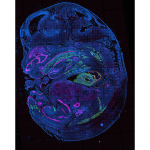

This is a 3D rendered light sheet Microscopy Image from human kidney cortex, generated by HuBMAP researchers Drs. Praveen Krishnamoorthy, Bo Zhang & Sanjay Jain at WUSTL.

Glomeruli – green spheres, Collecting Ducts – pink, Nerves – red